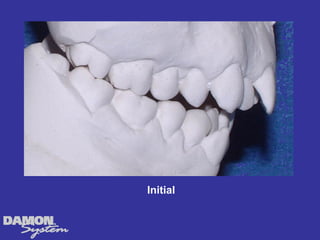

M.J. 14 yrs 6mos Class I severe crowding, deep bite, all Initial cuspids blocked out.

Initial 16 yearsโ€“ 5 months Class II, severe crowding, bilateral posterior crossbite